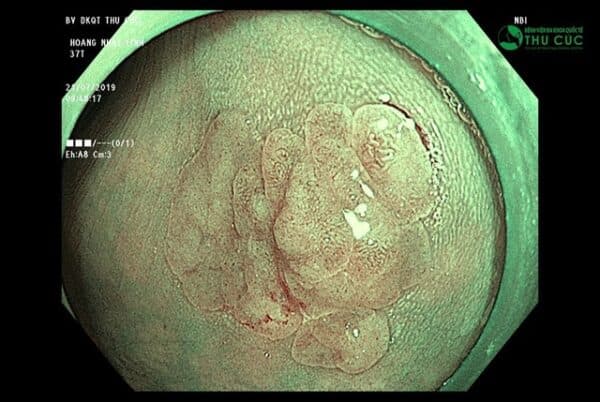

Nhiều trường hợp nuối tiếc vì không đi khám và nội soi sớm. Có trường hợp bệnh nhân thấy nhiều triệu chứng khó chịu trong 1 thời gian dài nhưng không đi kiểm tra, đến khi nội soi thấy có 1 khối u khá to trong lòng đại tràng, có dấu hiệu loạn sản, nghi ngờ ung thư. Nếu được phát hiện sớm hơn, u chưa phát triển lớn thì việc điều trị sẽ đơn giản và đỡ tốn kém hơn rất nhiều.

Không chỉ mang lại cảm giác dễ chịu cho người bệnh, công nghệ nội soi NBI 5P đang được ứng dụng tại Bệnh viện Thu Cúc còn có khả năng phát hiện những tổn thương bất thường bao gồm cả ung thư tiêu hóa ngay từ sớm và rất sớm.

Do sử dụng ánh sáng dải tần hẹp với hai bước sóng 415nm và 540nm, nội soi NBI có thể giúp quan sát sâu và sắc nét dưới lớp niêm. Nhờ đó bác sĩ có thể phát hiện các tổn thương, khối u, tổ chức tiền ung thư ngay từ khi mới khởi phát. Bên cạnh đó, công nghệ nội soi NBI còn có khả năng phóng đại hình ảnh tới hơn 100 lần nhờ ứng dụng công nghệ Dual Focus hiện đại nhất thế giới, cho phép ống soi tiếp cận vị trí tổn thương ở khoảng cách gần nhất (từ 2 đến 6mm). Với ưu điểm này, nội soi NBI giúp bác sĩ dễ dàng đánh giá tổn thương bề mặt và mạch máu bên dưới đường tiêu hóa, xác định tổn thương đó có nghi ngờ ung thư hay không qua hình ảnh.